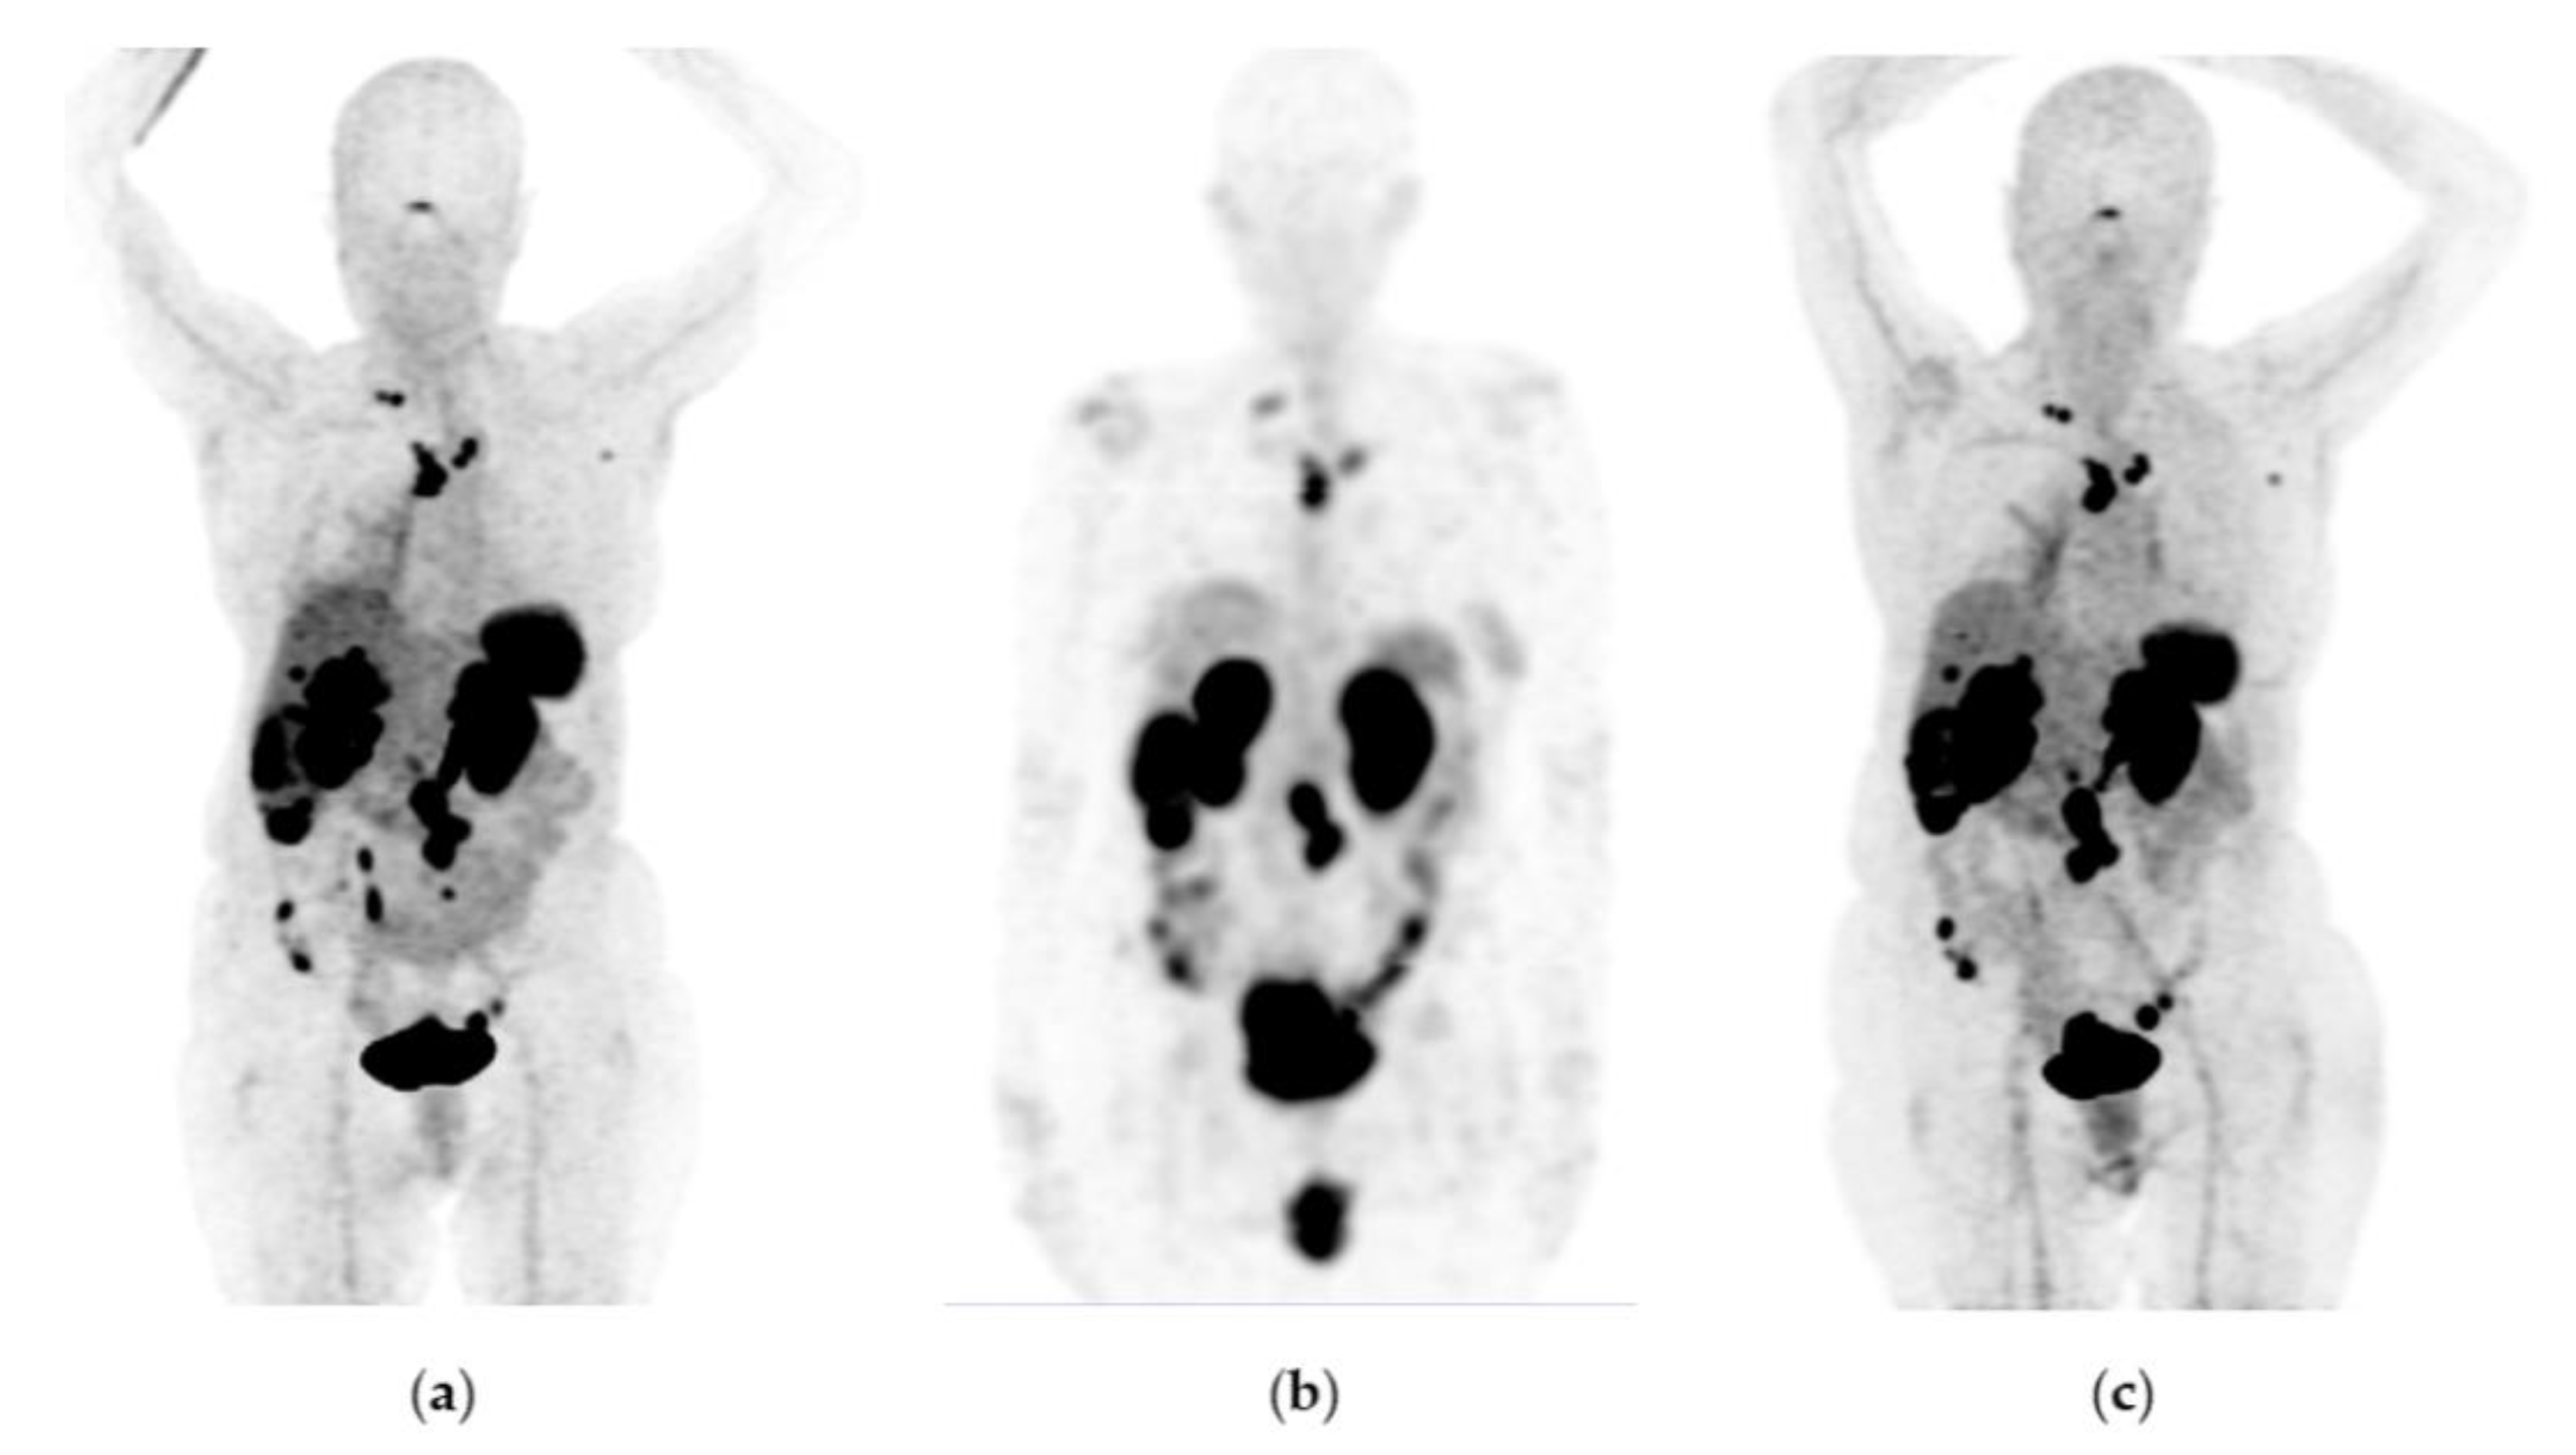

Figure 6. A 65-year-old woman was diagnosed with a well-differentiated neuroendocrine tumor of the intestine with metastases to the liver, mesenteric nodes, and abdominal implants. Due to disease progression, she was considered a candidate for therapy with 177Lu-DOTATOC (four doses of 7.4 GBq) in combination with octreotide. Response: partial response. She did not show any hematologic side effects. The last renal scintigraphy showed a slight decrease in renal tubular function with no changes compared to previous scintigraphy. (a) 68Ga-DOTATOC PET/CT imaging before 177Lu-DOTATOC therapy, (b) 177Lu-DOTATOC SPECT imaging (first dose), (c) 68Ga-DOTATOC PET/CT imaging one year after the first 177Lu-DOTATOC therapy.

Figure 7. A 48-year-old woman was diagnosed with a metastatic neuroendocrine tumor of the ileum. She received 177Lu-DOTATOC (four doses of 7.4 GBq) in combination with octreotide. Response: stable disease. No hematologic or renal toxicity. (a) 68Ga-DOTATOC PET/CT imaging before 177Lu-DOTATOC therapy, (b) 177Lu-DOTATOC SPECT imaging (first dose), (c) 68Ga-DOTATOC PET/CT imaging one year after the first dose of 177Lu-DOTATOC.

Figure 6, Figure 7 and Figure 8 show typical clinical cases of partial response and stable disease after 177Lu-DOTATOC therapy (the stable disease does not meet the criteria for partial response or progressive disease).